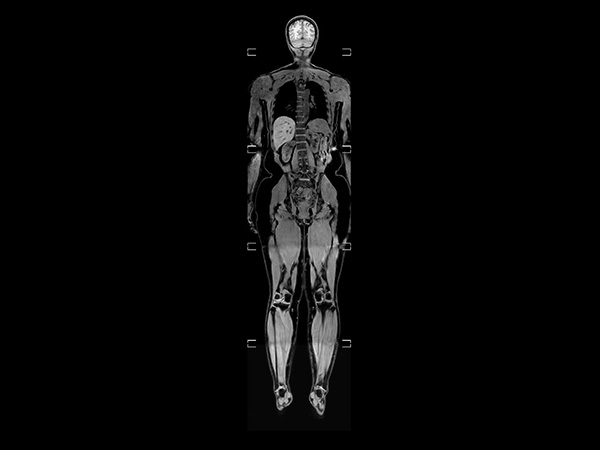

Helium-free MR operations: Wholebody imaging under 30 minutes